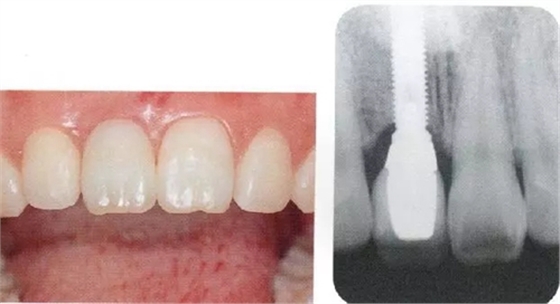

▲圖44-1,2

圖44-3

圖44-1~3 22歲,女性。交通事故3個月后來院。由于事故導(dǎo)致上頜右側(cè)前牙區(qū)凹陷且存在牙根吸收現(xiàn)象。圖片為初診時的前方照與根尖片。

▲圖44-4,5

圖44-6

圖44-4~6 拔牙后通過骨移植材以及結(jié)締組織移植(CTG)進行GBR。

▲圖44-7,8

7個月后,牙齦組織的愈合狀態(tài)。

▲圖44-12,13

圖44-12 種植體植入4個月后。二次手術(shù)時同時進行結(jié)締組織移植(CTG),以增大牙齦。

圖44-13 二次手術(shù)后的狀態(tài)。

圖44-14

同時期的X光片。

▲圖44-15,16